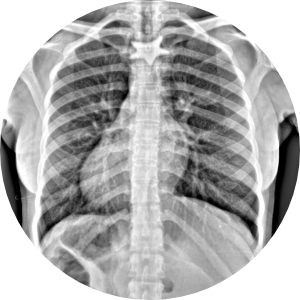

Humanos

• Niños

• Adultos

• Pacientes geriatras

HumanosRadiología Digital Directa

Posteriormente la radiología computarizada evolucionó a la radiología digital directa en donde podíamos hacer placas radiográficas y ver las imágenes en aproximadamente 18-20 segundos después de tomar la radiografía, y esto fue un gran avance para la comunidad de médicos, veterinarios, antropólogos, restauradores, paleontólogos, investigadores, y gente que requería radiografías y que por la logística que se requería y lo que implicaba no utilizaba esta herramienta de diagnóstico. En la actualidad, en la era de la inmediateidad podemos tomar placas radiográficas de alta definición en 2-3 segundos, en lugares remotos, sin necesidad de energia electrica ya que los generadores de rayos X funcionan con baterías, así como los equipos de radiología digital directa, esto ha permitido que el servicio de radiología se pueda proporcionar en cualquier lugar donde se requiera, pudiendo llevarse a donde están los pacientes u objetos a radiografiar, con las ventajas que esto implica. Los equipos actuales son ligeros, portátiles, de alta frecuencia, de alta definición, se ha optimizado la radiación que generan, lo que permite obtener imágenes radiográficas de muy buena calidad, con técnicas radiográficas inferiores a lo que se requería con radiología análoga. Hoy en día manejamos radiología digital directa de alta resolución.

Ideal para pacientes con incapacidad para trasladarse al hospital o moverse. Fracturados, con fijación externa, osteoporosis, niños, adultos, pacientes geriatras, seguimiento post cirugía ortopédica.